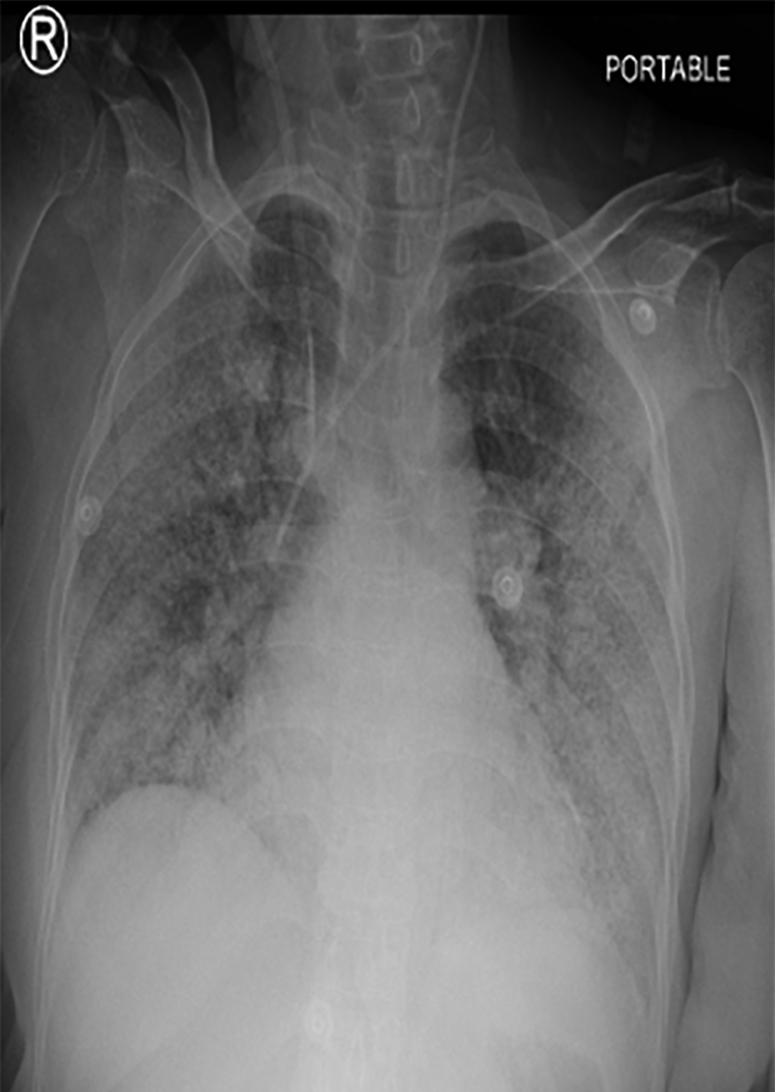

In April 2021, a 66-year-old female presented to our institute with shortness of breath, malaise, and sore throat. Upon presentation, she was drowsy and hypoxemic, with a respiratory rate of 24 breaths/minute and oxygen saturation of 55% on room air, a pulse rate of 84 beats/min, and blood pressure of 140/69 mmHg. After receiving 15 L/min of oxygen via a non-rebreather mask, her oxygen saturation improved to 92%. Her laboratory workup showed raised inflammatory markers (white cell count of 13.81 × 109/L, absolute neutrophil count of 10.6 × 109/L, and C-reactive protein of 269 mg/L), acute kidney injury (creatinine of 608 µ/L, potassium of 6.7 mmol/L, sodium of 126 mmol/L, urea of 23.1 mmol/L), normal hemoglobin (11 g/dL) and troponin T 28.4 ng/L, and liver function tests were unremarkable (alanine aminotransferaseof 34 IU/L, aspartate aminotransferase of 49 IU/L, and alkaline phosphataseof 185 IU/L). A semi-erect anteroposterior portable chest X-ray revealed bilateral infiltrates suggestive of COVID-19 pneumonia [Figure 1]. The patient tested positive for COVID-19 and was started on intravenous dexamethasone, ceftriaxone, frusemide, and gentle hydration. She was admitted with the impression of acute respiratory distress syndrome secondary to COVID-19.

Figure 1: A semi-erect anteroposterior portable chest X-Ray showing bilateral infiltrates, suggestive of COVID-19 pneumonia.